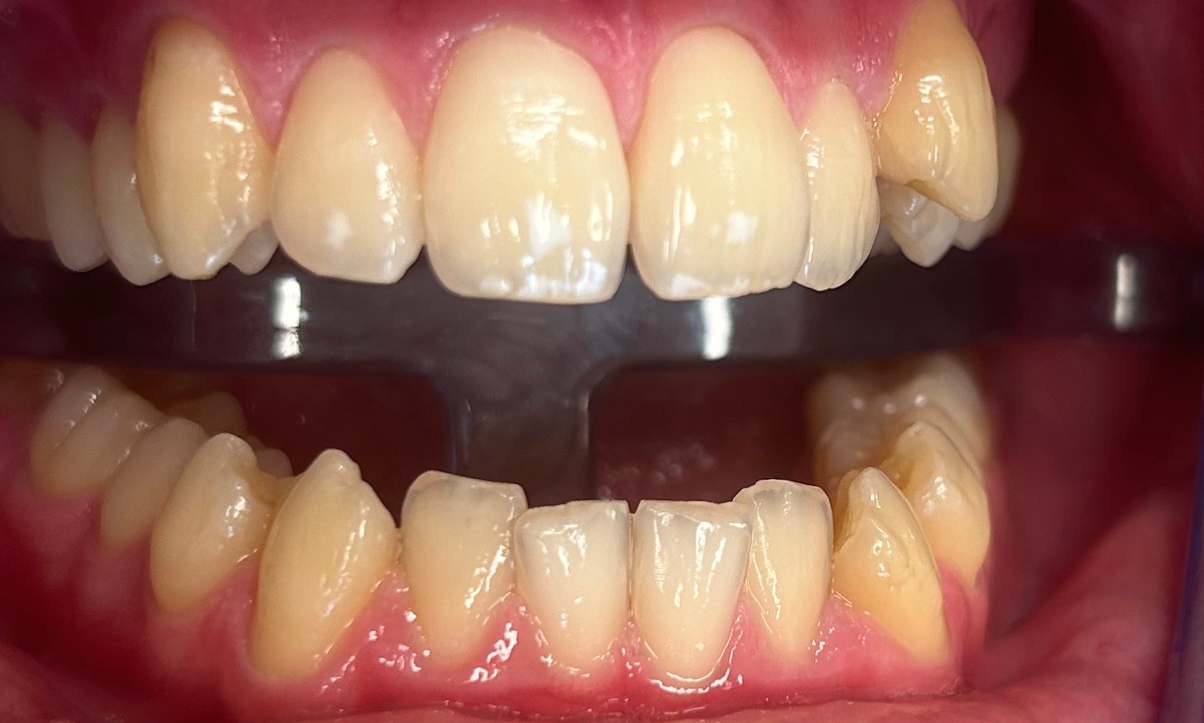

Poprawa estetyki uśmiechu: wybielanie zębów.

Profilaktyka i estetyka: usuwanie kamienia i wybielanie.